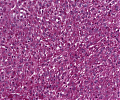

Follikuläres_NHL_A96.png

Lymphomgewebe mit Proliferation unreifer Zentroblasten und Zentrozyten

A52 Hodgkin-Lymphom

Mehrkernige Reed-Sternberg Zelle mit mit prominenten Nukleoli beim klassischen Hodgkin-Lymphom.

Multiples Myelom

Erkennbar sind dicht gepackte plasmazytoide Tumorzellen.